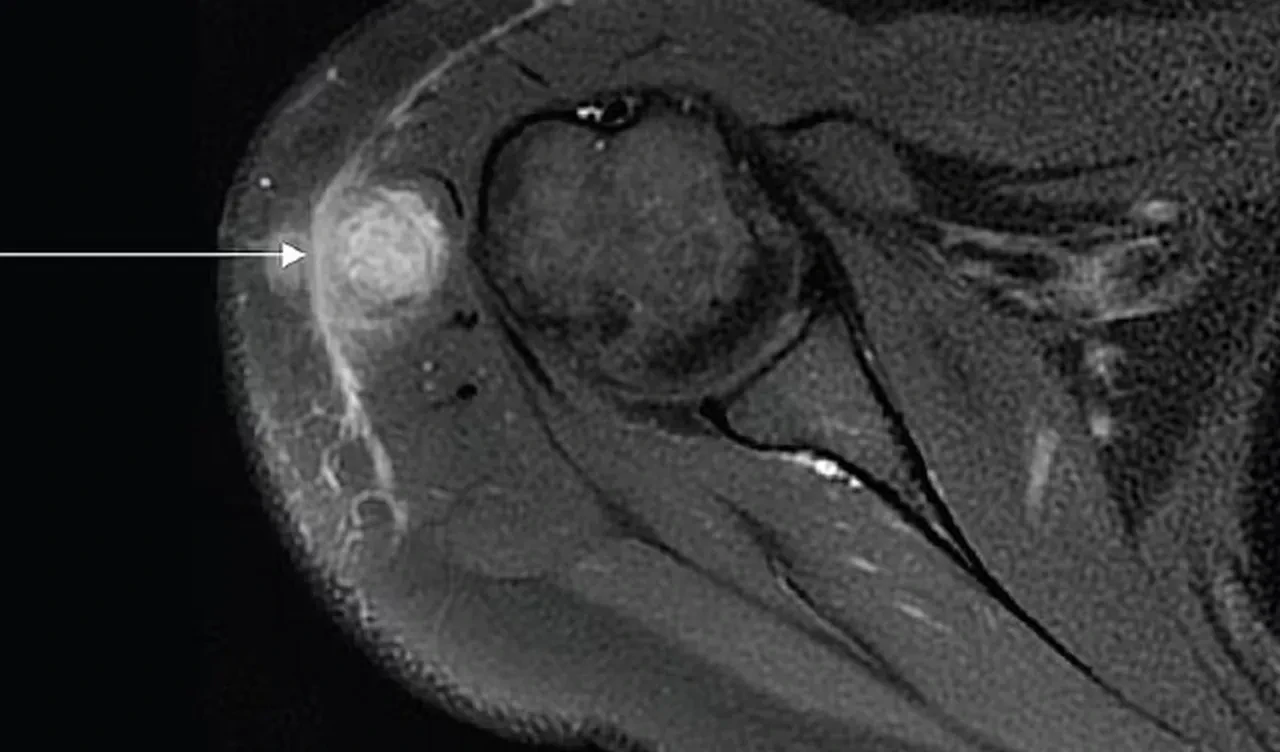

Yanlış yapılan aşının ardından kadının kolunda bir iltihaplı apse meydana geldi. Doktorlar ilk olarak bunun ciltteki bağ dokusu iltihabından kaynaklandığını düşündü. Fakat testler daha farklıydı. Testlere göre, apsenin vereme neden olan bakteri içerdiği ortaya çıktı.

Ayrıca BCG aşısının deri altına değil kas içine enjekte edildiği anlaşıldı. Dailymail'in haberine göre, yapılan bu ikinci hata da enfeksiyonun kontrol edilemez hale gelmesine ve yayılmasına neden oldu.